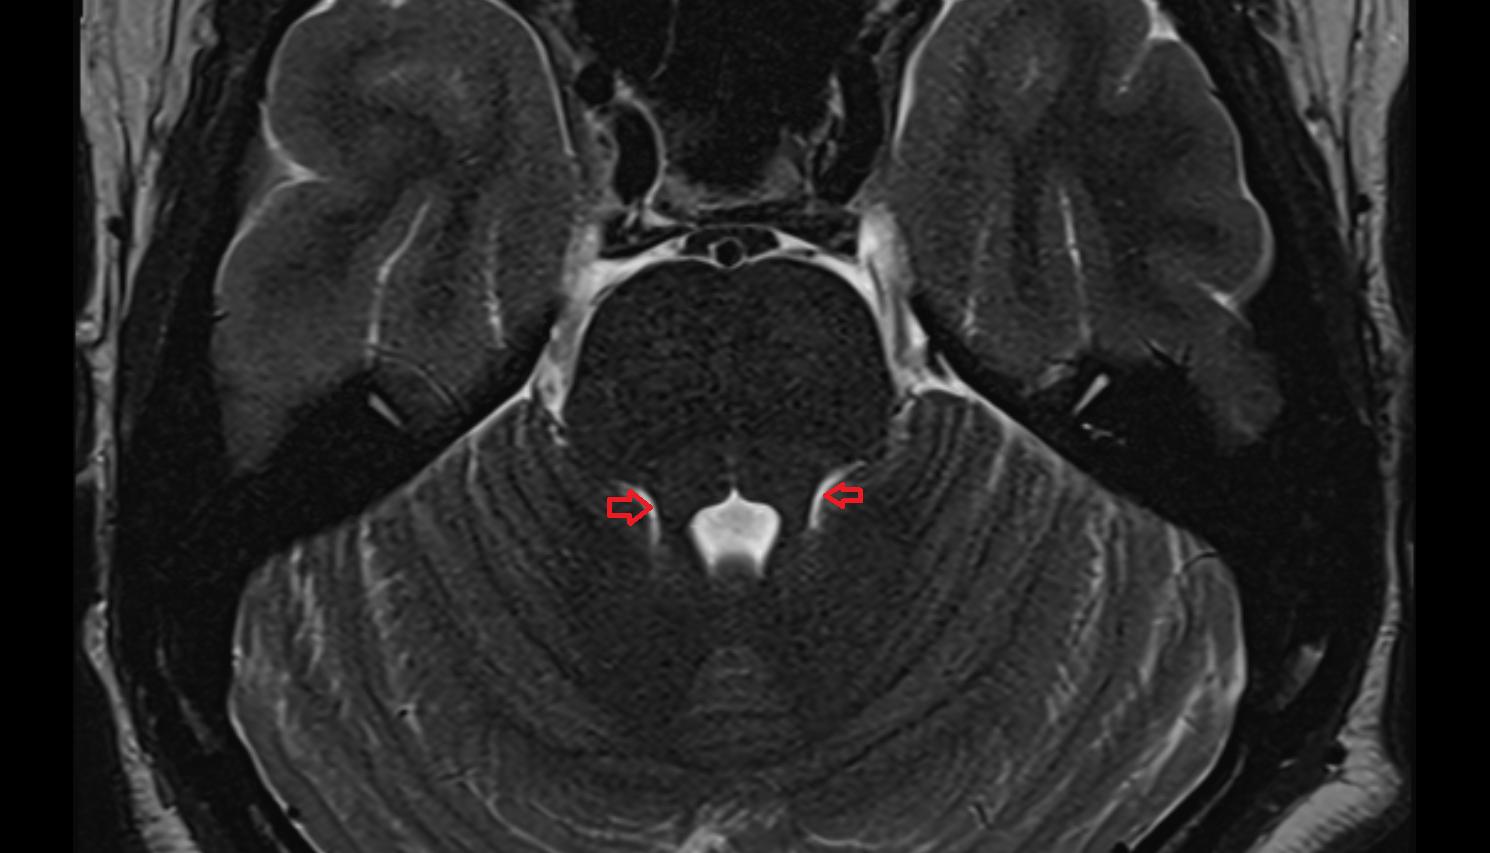

- Cerebellum

- Tonsil of cerebellum

- Cerebellar tonsil (H IX)